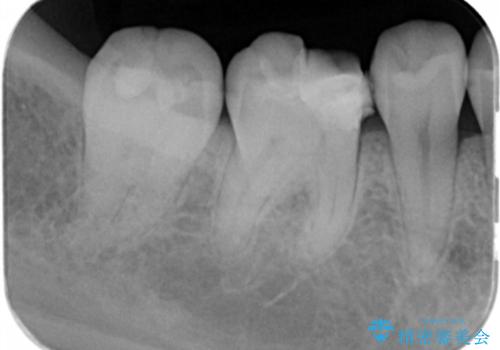

- 歯が欠けたとの事で来院。プラスチックの樹脂で治療されたところが欠けていて中に虫歯が再発していました。

古い樹脂と虫歯を拡大鏡下でしっかり取り除き、ジルコニアクラウンにて治療しました。